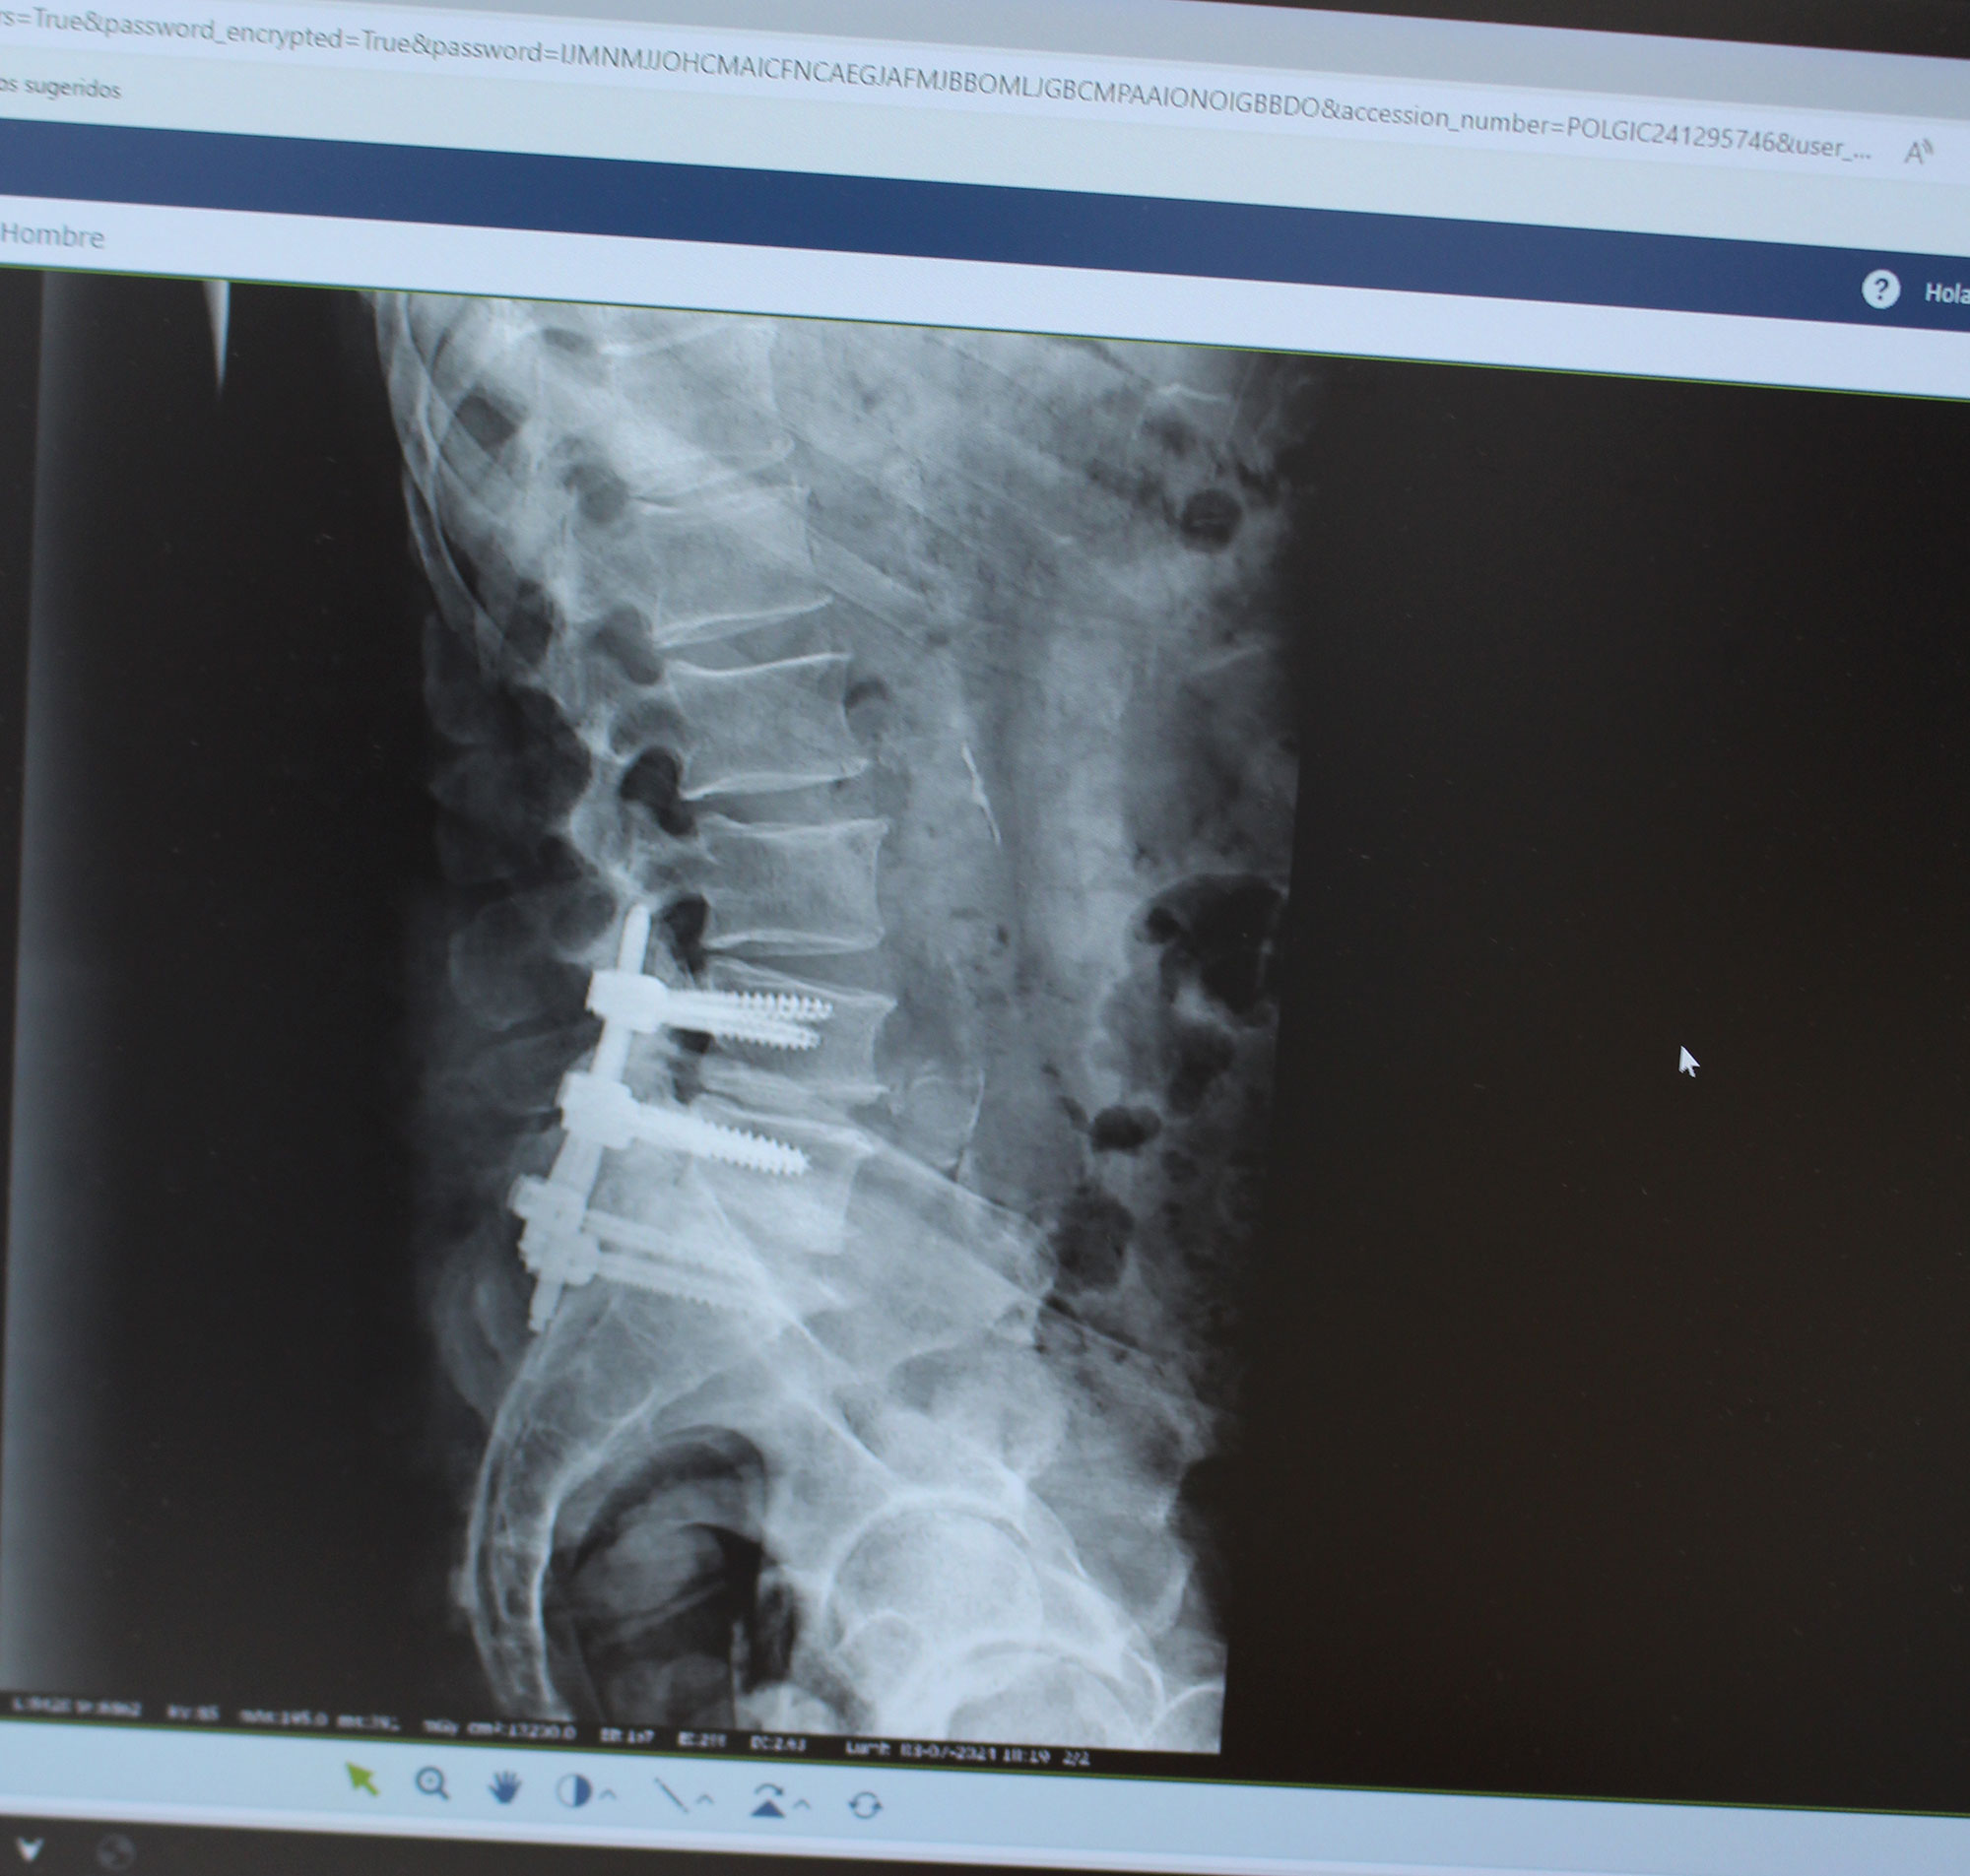

Tratamiento quirúrgico

Artrodesis vertebral, estabilización vertebral mediante la unión de dos o más segmentos vertebrales a través de un injerto óseo obtenido de la creta ilíaca posterior.